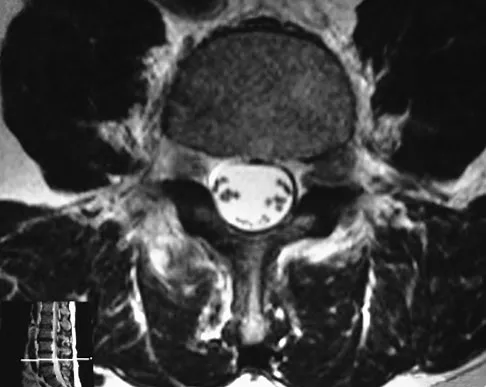

Question 53

The MRI findings shown in Figure 51 would most likely create which of the following signs and symptoms?

Explanation